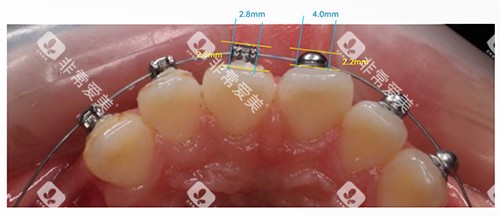

牙齿矫正

• 传统矫正:金属托槽矫正6000元起,适合青少年及追求经济实惠的成人;

• 舒适美观:陶瓷半隐形矫正10000元起,兼顾矫正结果与美观度;

• 高端隐形:隐形矫正(如时代天使)12000元起,适合对美观要求极高的患者。